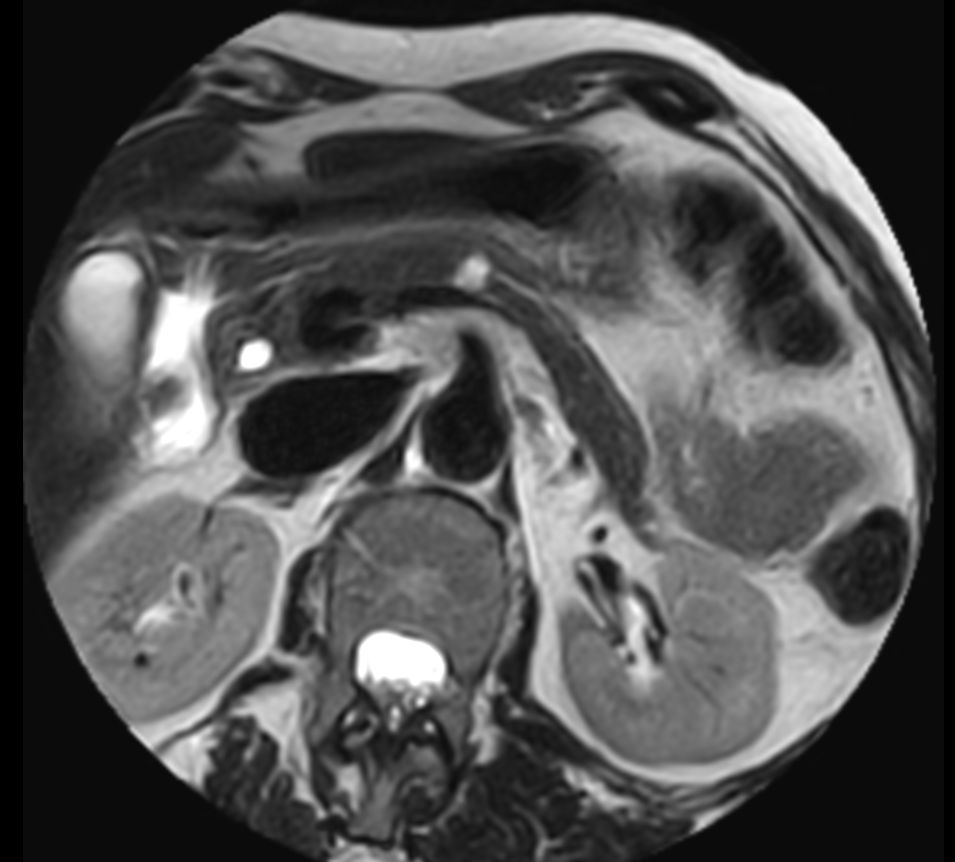

Pancreas nodule – Free breathing

Patient with a pancreas nodule. ExamCard includes Compressed SENSE to shorten the breath hold time, VitalEye for touchless respiratory sensing, MultiVane XD to acquire motion-free diagnostic images and 4D FreeBreathing to perform multi-phase contrast-enhanced Liver MRI studies.

T2w SPAIR - Breath hold